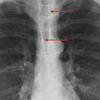

AzyEsop interf

Ex 1 arrows

Date: 03/23/2004

Views: 2892